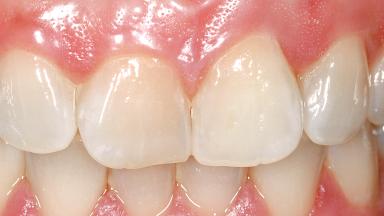

A 29-year-old female patient presented for treatment to replace the upper left central incisor tooth with an implant- supported restoration. The tooth had been intermittently symptomatic for the previous 12 months. The tooth had originally suffered trauma about 15 years previously. Several endodontic treatments had been performed, including an apicectomy procedure to retain the tooth. The patient was healthy and a non-smoker. She had reasonable expectations in regard to esthetic outcomes and the risk of marginal tissue recession following treatment. At medium smile, the gingival margins of the upper teeth were visible, with a display of 3 to 4 mm of the gingival margins. Gingival recession of tooth 21 and a discrepancy in the gingival levels between teeth 11 and 21 was observable during normal speech and smile.